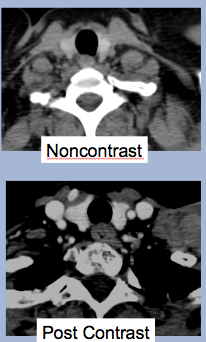

Dx?

Normal CT